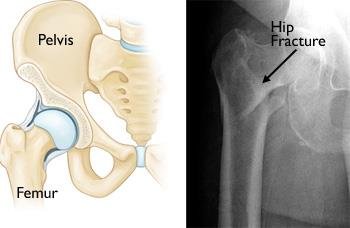

Hip Joint Fracture

Hip Joint Fracture : Successfully Operated by…